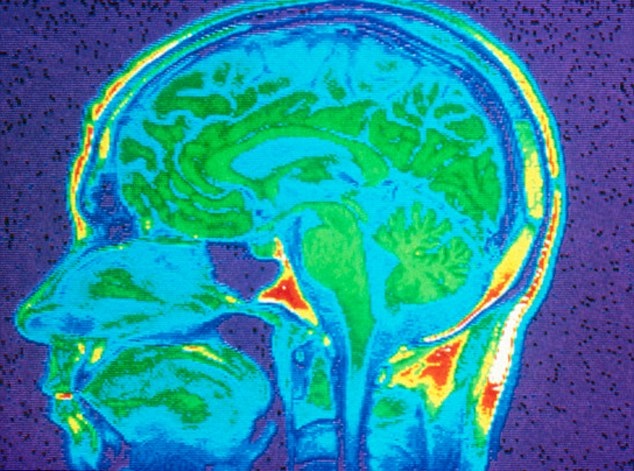

研究员指出,人体内有一种名为SKA2的基因,负责调节脑部回应压力的贺尔蒙水平,若其功能被化学物“甲基群”(methyls)伤害,脑部便无法抗衡压力贺尔蒙,导致压力日积月累,令人出现自杀念头。

研究员早前研究了150名健康人士及自杀死亡的死者脑组织样本,发现自杀者的甲基群浓度较高,SKA2基因水平亦相低较低。 研究员其后为325名受试者进行血液检测,看看上述发现可否预测自杀风险。结果发现,借由观测SKA2基因来预测一个人产生自杀念头或行为,准确度高达80%至90%。